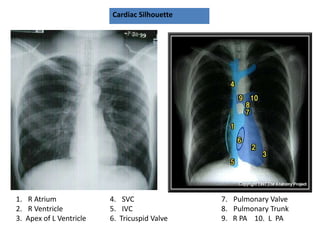

Cardiac Silhouette

1. R Atrium

2. R Ventricle

3. Apex of L Ventricle

4. SVC

5. IVC

6. Tricuspid Valve

7. Pulmonary Valve

8. Pulmonary Trunk

9. R PA 10. L PA